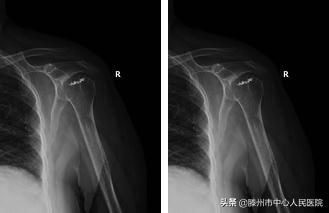

患者老年女性,71岁,40余天前摔伤后出现右肩关节疼痛、活动受限,于我市某医院就诊,经过保守治疗无效,严重影响生活质量。患者于3月13日来我院行右肩MRI检查示:右肩关节脱位、右肩袖损伤、右肩诸肌损伤、右肩关节盂唇损伤、右肩关节积液,收入院。入院诊断为“1、右肩关节陈旧性前脱位 ;2、右肩关节Hill-Sachs 损伤;3、右肩关节Bankart损伤;4、右肩冈上肌腱损伤 ;5、右肩肱二头肌长头腱脱位。” 完善术前检查后,为该患者在全麻下进行“右肩关节镜松解+肩关节脱位复位+冈上肌腱缝合固定+Bankart损伤修复+remplissage手术”,手术过程顺利,术后恢复良好,患者肩关节症状明显改善。

术前患者肩关节功能情况

术后4个月患者肩关节功能情况,患者恢复满意